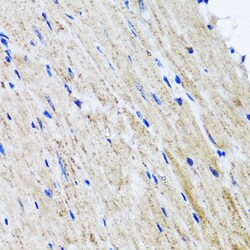

Immunogen sequence: RWAFNWDTKD IYRQRSRALV QAQHPDWPAP QVEAVAQDQF QGAARAWMAG TLQLGRALRP RGLWGFYGFP DCYNYDFLSP NYTGQCPSGI RAQNDQLGWL WGQSRALYPS IYMPAVLEGT GKSQMYVQHR VAEAFRVAVA AGDPNLPVLP YVQIFYDTTN HFLPLDELEH SLGESAAQGA AGVVLWVSWE NTRTKESCQA IKEYMDTTLG PFILNVTSGA LLCSQALCSG HGRCVRRTSH PKALLLLNPA SFSIQLTPGG GPLSLRGALS LEDQAQMAVE FKCRCYPGWQ APWCERKSMW; Positive Samples: Mouse liver, Mouse lung; Cellular Location: Lysosome.

This gene encodes a lysosomal hyaluronidase. Hyaluronidases intracellularly degrade hyaluronan, one of the major glycosaminoglycans of the extracellular matrix. Hyaluronan is thought to be involved in cell proliferation, migration and differentiation. This enzyme is active at an acidic pH and is the major hyaluronidase in plasma. Mutations in this gene are associated with mucopolysaccharidosis type IX, or hyaluronidase deficiency. The gene is one of several related genes in a region of chromosome 3p21.3 associated with tumor suppression. Multiple transcript variants encoding different isoforms have been found for this gene.

| ELISA, Immunohistochemistry (Paraffin), Western Blot, Immunocytochemistry | |

| Recombinant fusion protein containing a sequence corresponding to amino acids 136-435 of human HYAL1 (NP_1493492). | |